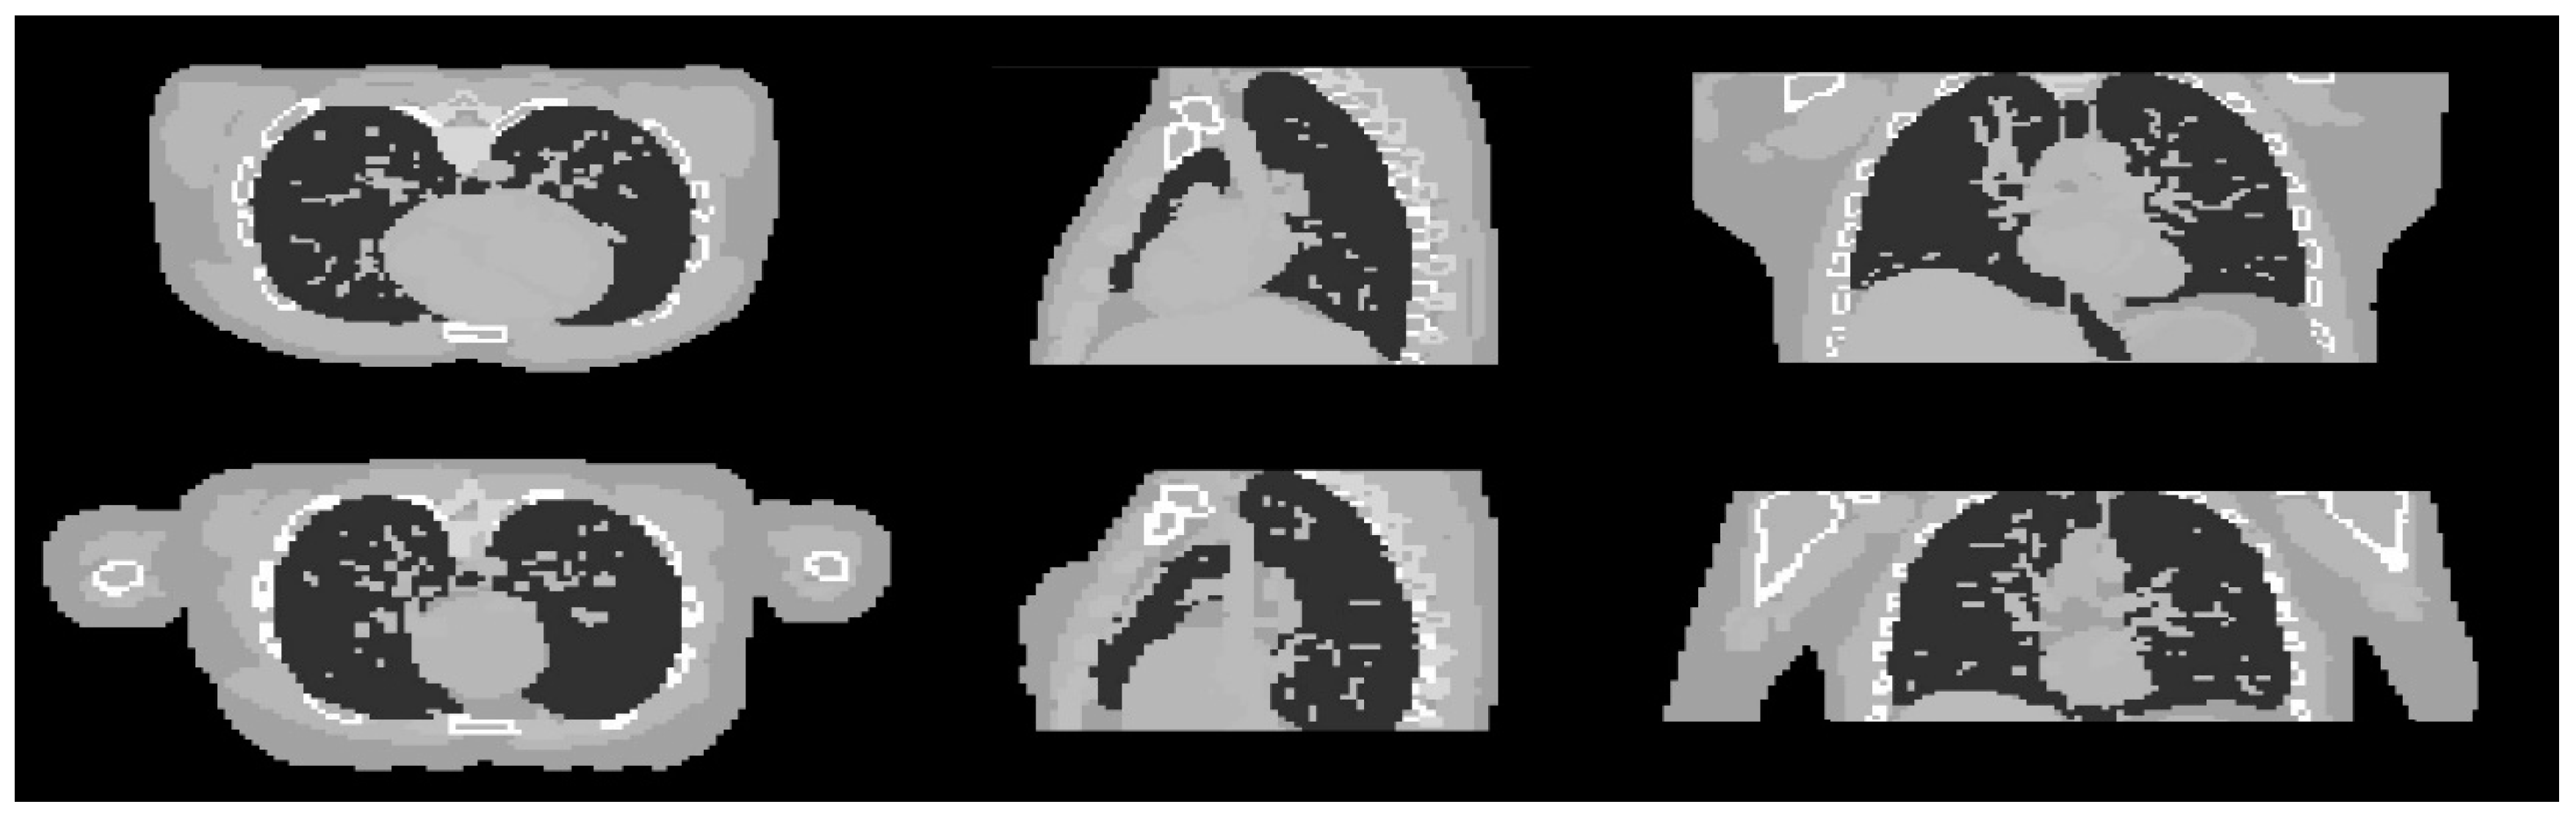

In this part, the robustness of the proposed algorithm was evaluated by applying the trained hyperparameter setting to the reconstruction of different samples. Two different XCAT phantom datasets were generated with different parametrisation from the training dataset. The first dataset is a male phantom with the chosen voxel size of 128 × 128 × 70. The second one is a female phantom with some modifications of the general parameters used to generate the phantom. The detail of the different modifications between these two phantoms is shown in Table 4. Cross-sectional slices of the two phantoms are shown in Figure 10.

Figure 10.

Cross sectional slices of the male (top row) and female (bottom row) phantoms in the three axes.